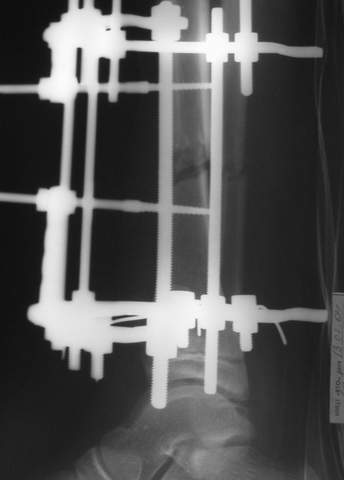

3a

3b

3c

В аттачте № 3 - один из примеров полукольцевого аппарат...

Это уже я баловался.

Итог? Работы больше (по времени и

интраоп "подгонке"), срастается также, а особого преимущества по сравнению с

"чиста" кольцевым (вес, удобство ношения и пр.) - я, по крайней мере,

не нашел.

Теперь не балуюсь.